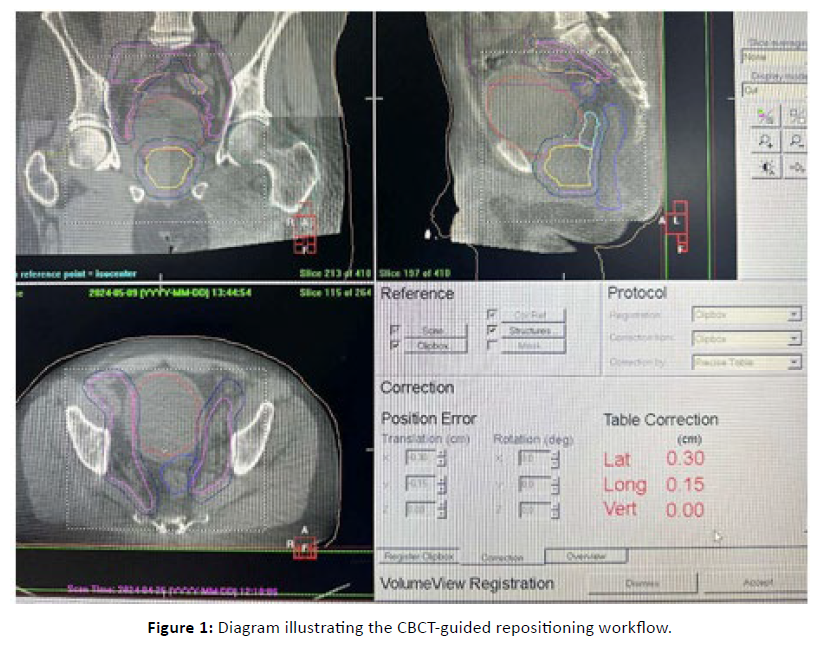

CBCT Acquisition and Repositioning

CBCT images (kV-XVI, Elekta) were acquired before each treatment session. They were registered to the simulation CT using automatic and manual matching procedures to quantify interfractional displacements along the three spatial axes:

- Left–Right (LR),

- Anterior–Posterior (AP),

- Superior–Inferior (SI).

Positional corrections were then applied through translational adjustments of the treatment couch [Figure 1].

Figure 1: Diagram illustrating the CBCT-guided repositioning workflow.